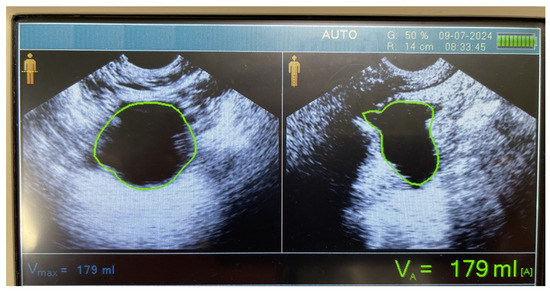

2.1. Ultrasound Assessment of Bladder Volume

2.2. Ultrasound Device